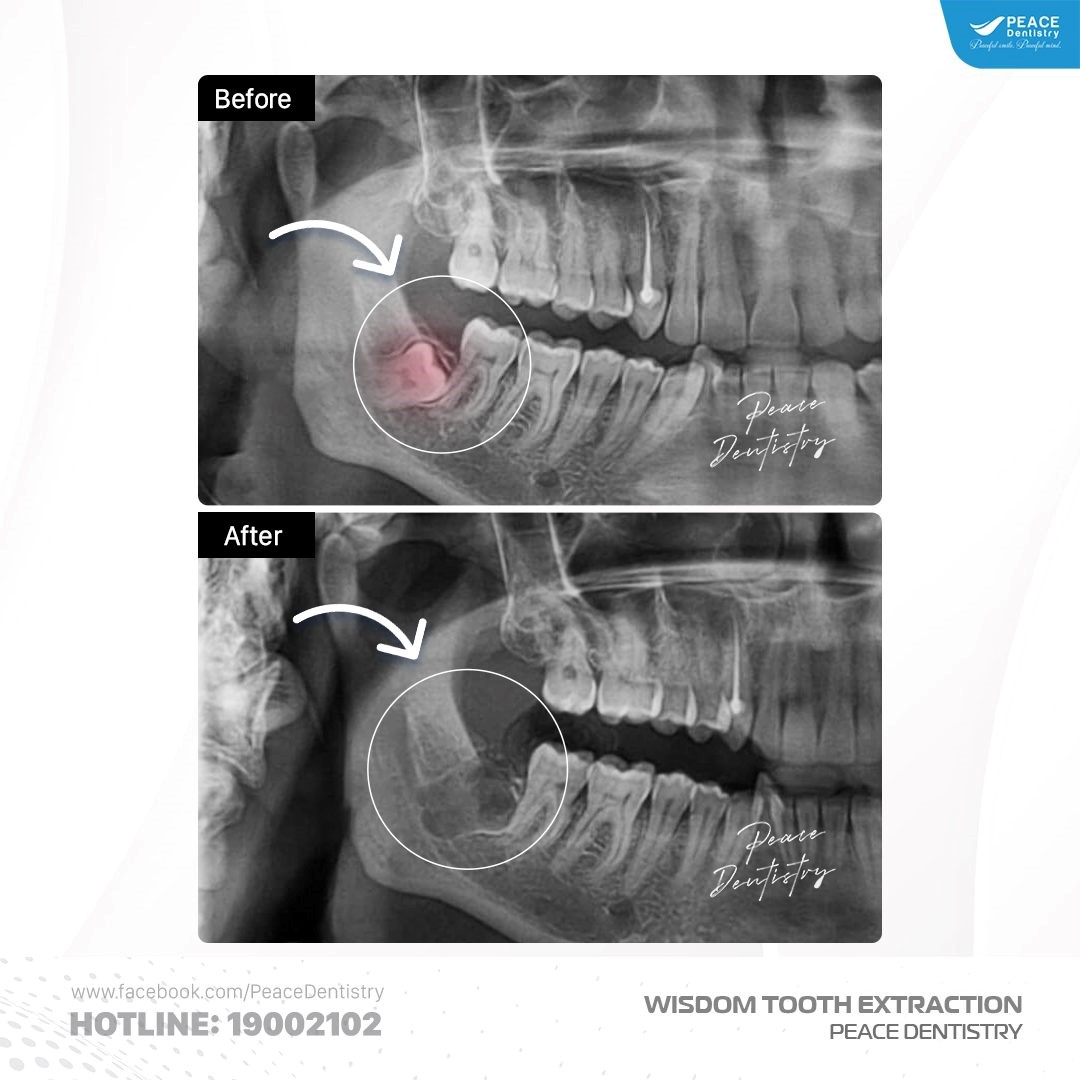

Tùy từng trường hợp, bác sĩ sẽ đưa ra hướng xử lý phù hợp:

(Kết quả nhổ răng khôn mọc ngầm hàm dưới được thực hiện tại Peace Dentistry)(**)